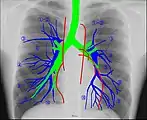

Anatomie radiographique d'une poitrine humaine. Anatomie radiographique d'une poitrine humaine.